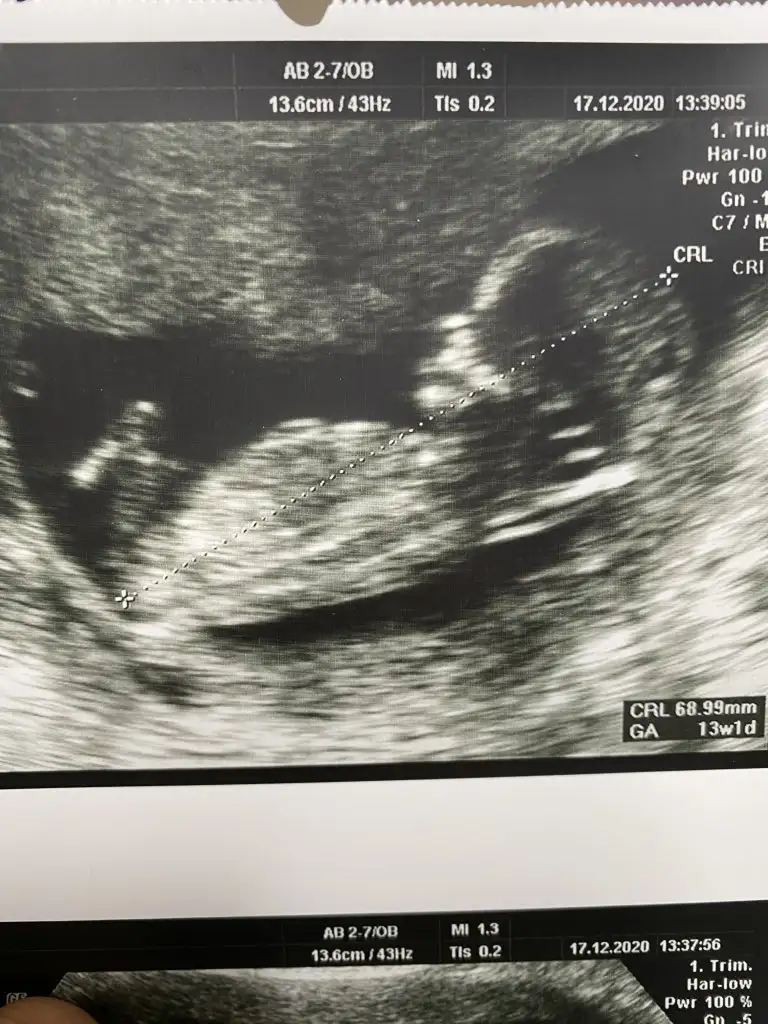

Ayy ağzın bal yesin inşallah Allah im sağlıklı hayırlı bir kız evlat nasip etsin isteyen her anneye ve banacanım senin attıgın usg de bebegi yandan görüyoruz ya ben kız gibi hissettim inan icimden öyle geldi kendi usg görüntülerime baktım video dan hep bir cıkıntı var bana erkek dendi 12. hafta dan beri sana erkege benziyor derken bacaklarının arasını gösterdi mi dr şuan pc den yazıyorum telden girip 14. hafta daki usg bacaklarının arasını atıcam hala senin kızın olucak gibi geliyor bana hayırlısı ama öyle geliyor ne yapayım :)